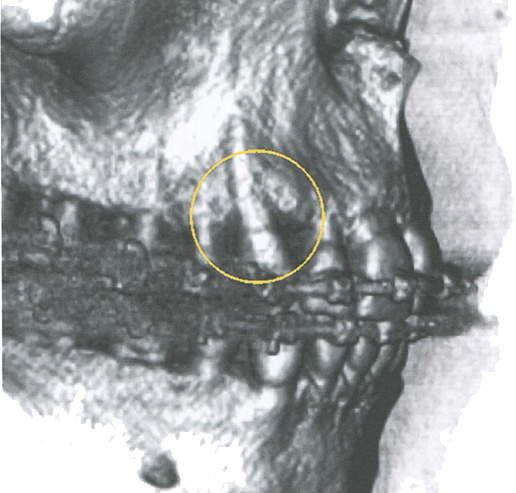

Особый интерес для врачей-ортодонтов представляет оценка торка зубов. Перемещения зубов проводятся внутри костной ткани, а именно, внутри губчатого вещества. Как только врач-ортодонт, не рассчитав границы, внутри которых он может перемещать зубы, выводит корни зубов за кортикальную пластинку альвеолярного отростка на верхней челюсти и альвеолярной части на нижней челюсти, возникают осложнения в виде фенестрации костной ткани и дегисценции (рис. 78).

Дегисценция костной ткани в области зуба

Рис. 78. Дегисценция костной ткани в области зуба 1.3, определенная на компьютерных томограммах в окне объемного рендеринга